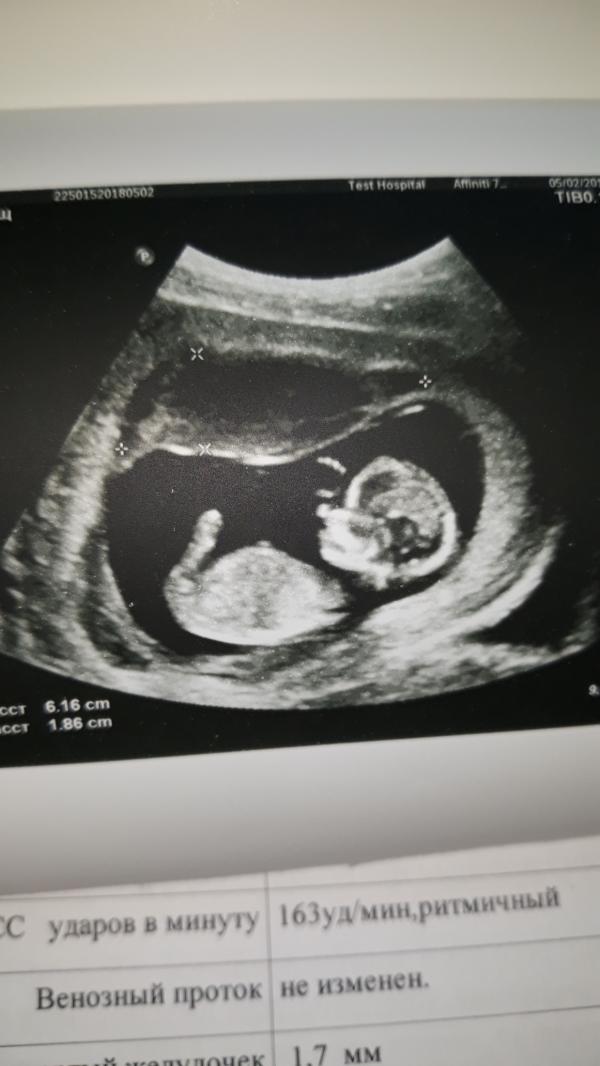

Узи скрининг на 12 неделе. сказали возможно мальчик.... у кого совпало такой прогноз?

Милашка такой (ая) 😍 Обожаю фото узи именно в 12 недель. Они такие маленькие крошки, но уже человечки 🤗 П.с у меня совпало